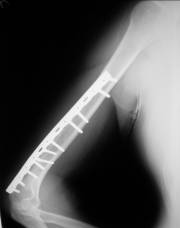

髓内钉

早在100多年前,就有人用不同的材料的棒状物进行过动物实验和临床观察,1918年,最早报告利用金属髓内钉固定治疗股骨干骨折。1953年德国人设计并使用了第一枚交锁髓内钉。

髓内钉的固定机制:

1、中央型内夹板式固定(钢板为偏心型固定)。

2、应力分散式固定,非应力遮挡式固定,有利于骨痂的塑形。

3、中心固定在理论上优于皮质外固定,可减小力臂,降低内、外翻成角及内固定失效的发生率。

4、为闭合复位或有限切开复位提供了基础。

胫骨交锁髓内钉:

胫骨钉的适应症:

1、胫骨中1/3稳定型骨折:横形骨折、短斜形骨折、假关节。

2、胫骨中部60%长度内的不稳定性骨折:干骺端附近的骨折、长螺旋形骨折、节段性骨折、粉碎性骨折、骨折伴骨缺损。

胫骨钉的特点:

多用于胫骨中段骨折。尽管也可用于胫骨近端和远端骨折,但并发症发生率较高,易发生畸形愈合。